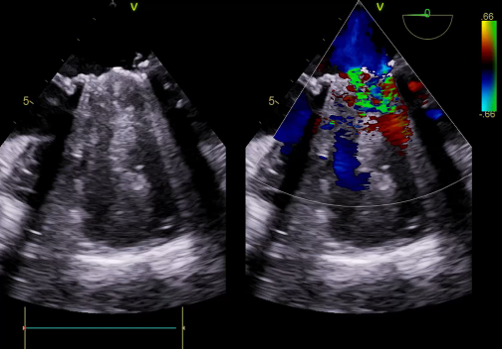

TEE, TEE and Floro showed both the leaflets to be stuck, almostno flow across the PV. The RV was higely dilated and there was severe RVdysfunction

Since TLT was not possible and surgeon refused for emergencyTranscatheter valve disruption was planned. The issues involve in the procedure were 1.Septal Puncture -due to pericardial patch in IAS, alteredanatomy due to Sx & ac dilatation of LA- Angle of puncture and Site ofpuncture. 2 Selection of wire3.Balloon- Size, make ( Compliant Vs NC), 4.Complication-like disc embolization, stuck disc leading to ac severe MA and strud fracture. The septa puncture was done as standard approach, a V18 wirewas parked in PV through a 7f Mullin sheath, Straight Turmo wire was was takenthrough a 6 JR to cross the valve and a 6 x 40 Armada balloon was dilatedacross the disc. Good acute result was obtained. The LA mean decreased from36-40 to 10-12mmHg. Post procedure the inotropic support, O2 demand decreasedover next 12 hr. However after 24 hr pt developed refractory RH failure and persistentanuria requiring SLED. And pt succumbed to the procedure 3 days after theprocedure.